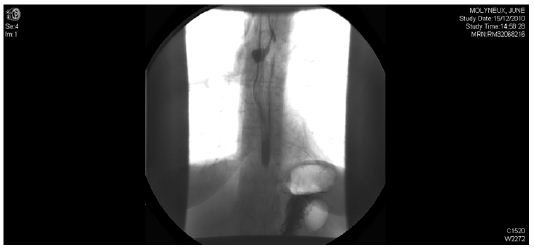

Repeat CT showed a small amount of contrast, identified within the gas containing mediastinal cavity which suggested a persistent small leak (Figure 2). The patient continued to be septic and did not improve as expected. Hence a repeat CT and contrast swallow was performed which demonstrated no leak in the cervical oesophagus, however there was a persistent defect. Contrast was noted to be leaking from a defect at the level of carina (Figure 3).

Figure 3: